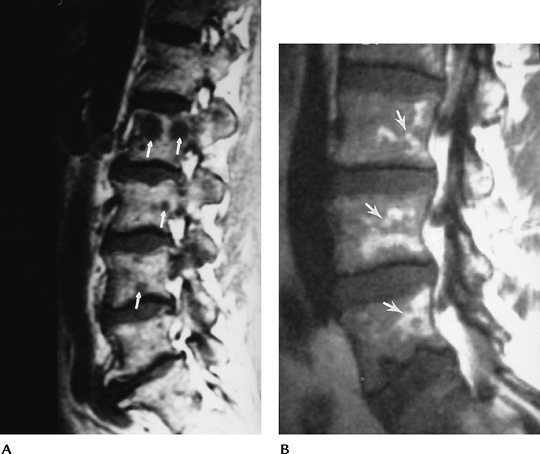

FIGURE 3-47 Type I endplate changes. Sagittal T1-weighted (A) and T2-weighted (B) images demonstrate decreased signal relative to marrow on T1-weighted (A) and increased signal on T2-weighted (B) images.

|

FIGURE 3-48 Type II endplate changes. Sagittal T1-weighted (A) and T2-weighted (B) images demonstrate increased signal relative to marrow on both T1- and T2-weighted sequences.

FIGURE 3-49 Type III endplate changes. Decreased signal (arrows) seen on both T1-weighted (A) and T2-weighted (B) images.